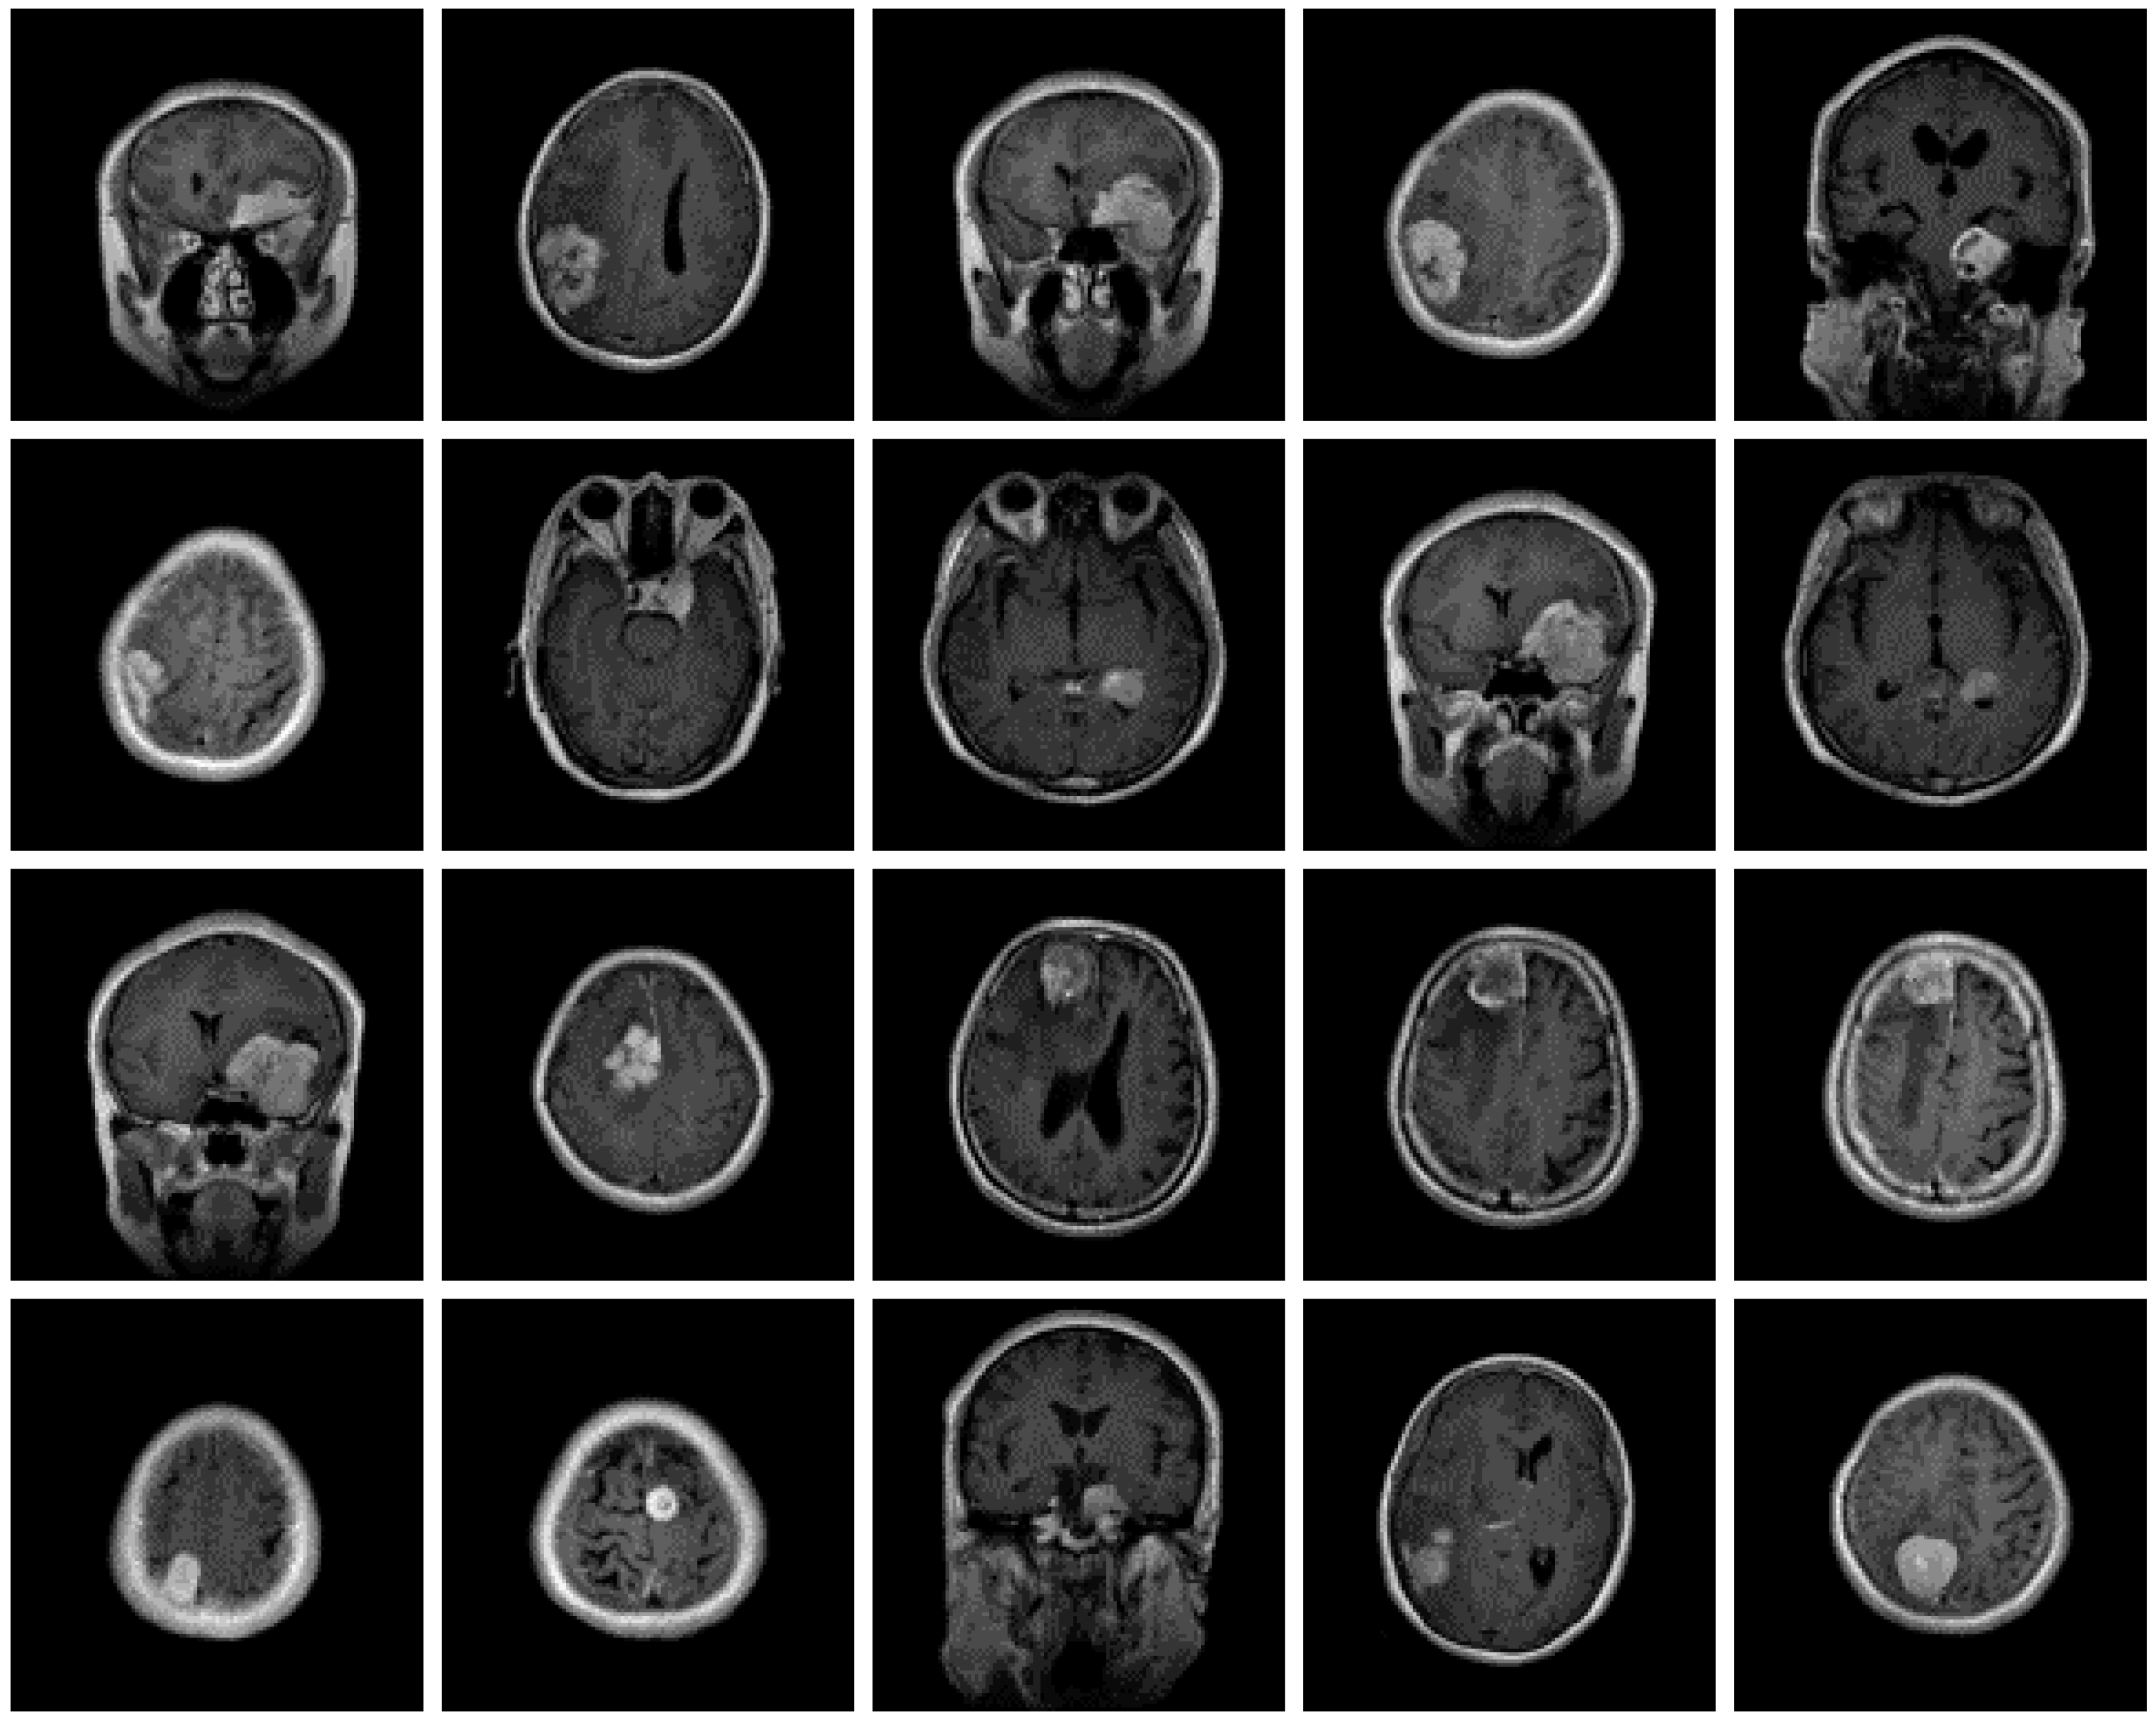

The dataset used for this current work is compiled from three other datasets: Figshare, SARTAJ, and Br35h. This composite dataset contains 2880 T1- weighted contrast-enhanced MRI brain images [26]. Gadolinium was used as contrast agent in these images. The target dataset has 829 images for glioma tumor, 825 images for meningioma tumor, 830 images for pituitary tumor and 396 images for no tumor cases. The images of the target dataset have a resolution of 512 × 512 × 3 with 24 bits color depth. Figure 1, Figure 2, Figure 3 and Figure 4 show some examples for each possible class: no tumor, glioma, meningioma, and pituitary tumor, respectively. The target dataset is split with 70% used for training and the remaining 30% kept aside for estimating the validation accuracy.

Figure 3.

Examples of MRI scans of meningioma tumors.